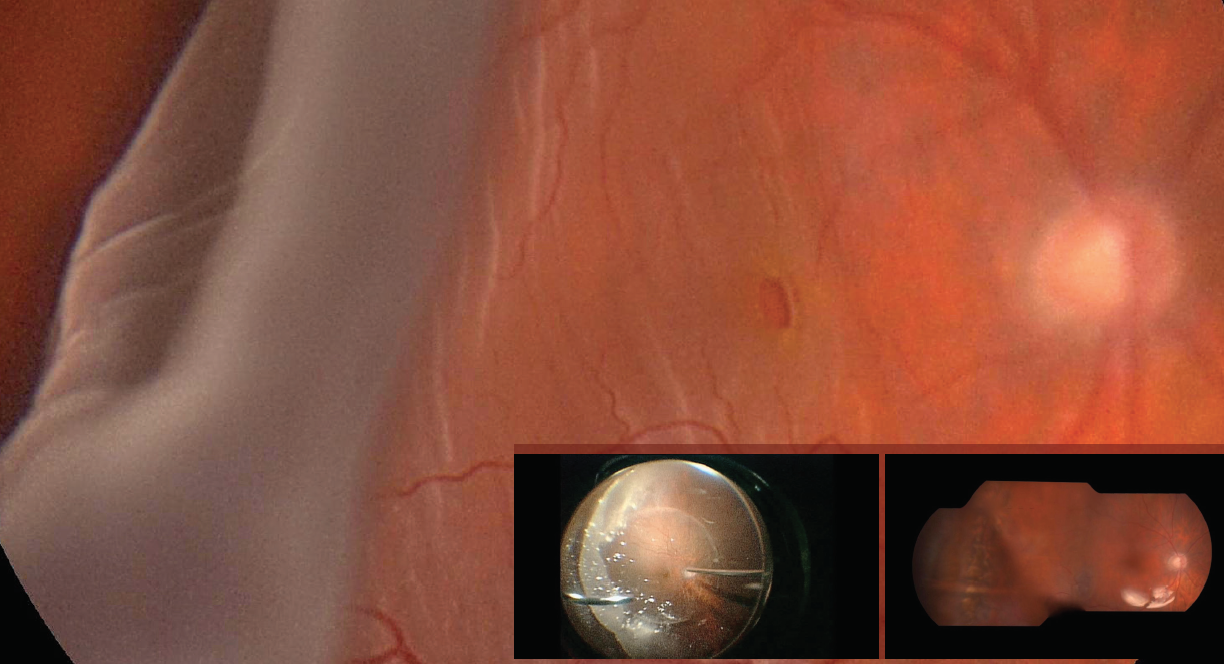

A 61-year-old man presented with a sudden reduction in vision in his right eye (OD) lasting 3 days. His BCVA at presentation was 20/200 in each eye (OU). He had a history of cataract surgery OD performed 4 years earlier. Slit-lamp examination showed a normal anterior segment with pseudophakia OD and advanced cataract in the patient’s left eye (OS). Fundus examination revealed a complete retinal detachment OD with a giant retinal tear that extended from the 7 o’clock position to the 11 o’clock position, another small retinal tear at 3 o’clock, and a full thickness macular hole (Main Figure).

Vitrectomy was performed using 23-gauge instrumentation. The edges of the tear were unrolled, and complete retinal reattachment was achieved under perfluorocarbon liquid. Intraoperative endolaser was performed around the peripheral retina for 360° and around the edges of the tears. Perfluorocarbon liquid was exchanged with silicone oil 5000 cs as final tamponade (Inset, left).

At the 6-month follow-up visit, the patient’s retina was attached and the macular hole was repaired. It is possible to appreciate the wide scar in the temporal quadrant as a consequence of the giant retinal tear and the surrounding laser photocoagulation (Inset, right). A mild rise in intraocular pressure was successfully managed with a combination topical beta blocker and carbonic anhydrase inhibitor. Silicone oil tamponade remains in situ and is scheduled to be removed 9 months after the date of the primary vitrectomy. The patient’s BCVA is 20/125 OD.